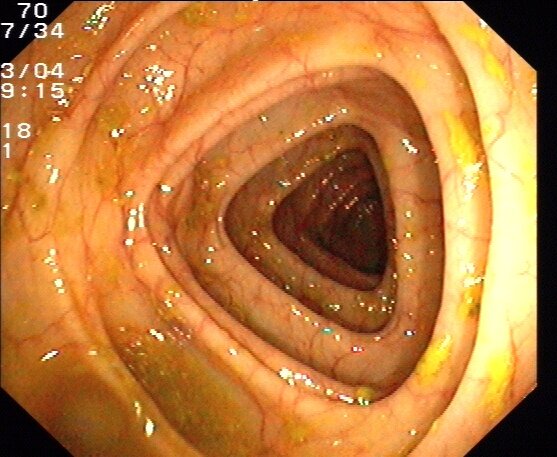

Na schemacie przedstawiono przekrój przez kosmek ze ściany jelita cienkiego człowieka.